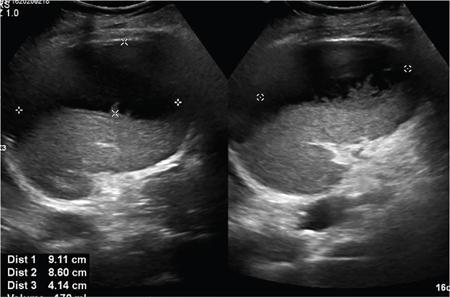

Vijay Kumar K.R. CONGENITAL SPLENIC ABNORMALITIES A multitude of variants and pathologies affect the spleen and it is pertinent for a radiologist to be aware of the common imaging appearances of the same. The spleen begins to develop in the fifth week of gestation from a mass of mesenchymal cells that condense between the two leaves of the dorsal mesogastrium. Several such aggregates fuse to form the lobulated embryonic spleen. The spleen is translocated to the upper left side of the abdominal cavity due to rotation of the stomach and differential growth of the dorsal mesogastrium. The mesogastrium fuses with the peritoneum over the left kidney and forms the splenorenal ligament. The lienorenal ligament fuses dorsally and the splenic artery courses behind the peritoneum as it enters the splenorenal ligament. The portion of dorsal mesentery between the stomach and spleen forms gastrosplenic ligament. Differentiated mesenchymal cells form the parenchyma, connective tissue and capsule of the spleen. The foetal spleen shows lobulations, which normally disappear before birth. However, they may persist along the medial part of the spleen. Sometimes a persisting portion of the spleen may extend medially and anteriorly over the upper pole of the left kidney. It may be mistaken for a space-occupying lesion arising from the kidney. Rarely it may extend posterior to the upper pole of the left kidney, displacing it anteriorly (Fig. 9.22.1.1). The notches and clefts along the superior borders are vestiges of the grooves that initially separated the foetal lobules. They may be 2–3 cm deep. They may mimic a splenic laceration in a patient with abdominal trauma, and the embedded peritoneum at the waist may simulate splenic infarction or haematoma. Hence caution should be exercised. A normal spleen which does not have a fixed ligamentous attachment can change position within the abdomen and is hence known as a wandering spleen. The spleen is normally anchored by the gastrosplenic and lienorenal ligament. Absence or weakness of one or more ligaments that affix the spleen. The spleen with its vascular pedicle as the sole attachment can become a hypermobile intraperitoneal organ. Rarely, the spleen may be normal in position with a wandering accessory spleen. Pregnancy (due to hormonal effects), prune belly syndrome, splenic cysts, malaria, Hodgkin’s disease and lymphangioma. Some of the affected patients may be asymptomatic and diagnosis may be incidental. Clinically it presents as a mobile, palpable, notched mass. Pressure on the vascular pedicle or torsion causes symptoms such as acute abdominal pain, nausea and vomiting. Torsion involving the tail of the pancreas may present as pancreatitis. Confirms the absence of spleen in the left upper quadrant of abdomen with identification of splenic tissue at an ectopic site. Power Doppler, colour Doppler and duplex sonography allow for the identification of blood flow in the splenic vessels and parenchyma. Intermittent torsion may be responsible for an enlarged spleen. Pathognomonic feature of wandering spleen is absence of the spleen in the upper abdominal cavity and presence of a well-demarcated, homogeneously enhancing mass of soft tissue in the pelvis or abdomen. Sometimes a wandering accessory spleen can be visualized as a long vascular pedicle connecting a small mass to the splenic vessels (‘jokari sign’). It can locate ectopic splenic tissue and can also indicate the viability of the tissue. Splenic vessel anatomy can be well demonstrated. 99mTc-sulphur colloid scintigraphy and heat denatured 99mTc-labelled red blood cell imaging provide useful information regarding size and location of splenic tissue. Torsion is indicated by lack of tracer activity in a previously demonstrated wandering spleen. Twisting and torsion of splenic artery can be demonstrated by celiac arteriography. The venous phase may demonstrate splenic vein obstruction with collateral circulation and varices. A congenital focus of normal splenic tissue that is separate from the main body of the spleen is known as an accessory spleen. It results from the failure of fusion of some embryonic splenic buds within the dorsal mesogastrium. Its incidence varies from 10% to 30% on autopsy examinations. They vary from a few millimetres to several centimetres in diameter. They most commonly are found around the splenic hilum. The second most common location is the pancreatic tail. They can also be found in the stomach wall, omentum, mesentery, large bowel and scrotum. Reveals a round or oval mass of tissue around the splenic hilum that is isoechoic with the main spleen. On noncontrast images they are isodense to the main spleen. CECT reveals serpiginous enhancement on arterial phase followed by homogeneous enhancement on venous phase-like spleen (Fig. 9.22.1.2). Accessory spleen is mildly hypointense to the spleen on T1 images and isointense on T2 images. Contrast administration reveals enhancement similar to that of spleen on the arterial, portal and late phases. It is isointense to spleen on DWI images with similar ADC values. 99mTc-sulphur colloid scintigraphy and heat denatured 99mTc-labelled red blood cell imaging show functional uptake in splenic tissue and differentiate splenule from other masses. PET CT-FDG avid mass can mimic tumour. Surgical resection is the preferred mode of treatment in the background of hypersplenism or lymphoma. It is characterized by an ectopic splenic tissue or an abnormal connection between the gonad and the spleen. The left side is more commonly involved than the right side. The accepted theory is that splenic gonadal fusion occurs due to abnormal attachment of the splenic anlage in the left dorsal mesogastrium with the left urogenital fold, during the fifth to eighth weeks of gestation. It has a higher male preponderance and can interfere with left testicular descent and closure of processus vaginalis. It commonly presents as inguinal hernia and cryptorchidism. The spleen and gonad are attached by a fibrous or splenic cord across the peritoneal cavity. It is associated with limb defect syndrome, cleft palate, micrognathia, anal anomalies, craniosynostosis, spina bifida, cardiac malformations, thoracic malformations and diaphragmatic hernias. This is not associated with congenital anomalies. Shows a well-defined scrotal mass with echotexture similar to that of spleen. Confirms splenic tissue in inguinal or scrotal area. It is characterized by the absence of spleen with duplication of right-sided structures. (Right isomerism). It has a slight male preponderance with an incidence of 1 in 40,000 live births. It has a poor prognosis due to its high association with congenital cardiac abnormalities (Fig. 9.22.1.3). It is of uncertain aetiology, and maybe associated with the mutations of CFC1 gene, SHROOM3 gene etc. Delayed development of embryonic curvature can be another cause. It is also theorized that it can be caused due to vascular compromise by pressure on splenic blood supply from adjacent structures. Splenectomy – Usually has a surgical history and is not accompanied by associated anomalies. It is a heterotaxy syndrome associated with multiple spleens and duplication of left-sided structures. (Left isomerism). It has an equal gender predilection with a slightly higher female preponderance. It has a fairly better prognosis than asplenia and is associated with a lesser incidence of cardiovascular anomalies (Fig. 9.22.1.4). It is of uncertain aetiology, and maybe associated with the mutations of CFC1 gene, SHROOM3 gene etc. Accelerated development of embryonic curvature can be another cause. SPLENIC INFECTION AND ABSCESS The infection of the spleen can show three patterns. Fungal and granulomatous infections usually present with multiple micronodules. A pyogenic abscess usually manifest as a solitary lesion. Imaging of diseases causing splenic nodules is never the sole basis for diagnosis. The clinical presentation and laboratory testing (tumour markers, tuberculosis testing and bone marrow biopsy) help in establishing an accurate diagnosis. The imaging findings are nonspecific and the nodules may vary in size from a few millimetres up to 2 cm in diameter. They maybe hypoechoic on ultrasound and hypoattenuating on CT. They are of low signal intensity on T1-weighted sequences and vary from hypointense to hyperintense on the T2-weighted sequences. The nodules show no enhancement or show ring enhancement after contrast study. Healed granulomas are seen as scattered, discrete, small calcifications in an otherwise normal spleen. With increasing number of immunocompromised patients, such as oncology patients undergoing aggressive chemotherapy, critically ill patients in intensive care units, injection drug abusers, and HIV-infected patients, there is rise in the incidence of splenic abscess. For splenic abscess to develop, it may require the presence of bacteremia (sepsis and septic emboli) and altered splenic architecture, which is caused secondary to a haematoma, infarct, or sickle cell disease. Abscesses can also develop from the extension of infection from adjacent organs, like in cases of infected pancreatitis and perinephric abscess, which are less common. In about 20% of cases, cause or source could not be discovered. Abscesses can be unilocular or multilocular, solitary or multiple, depending on the causative organisms and patient’s immunity. Mortality ranges from 15% in otherwise healthy patients with unilocular splenic abscess to 80% in immunocompromised patients with multiple abscesses. Abscesses which are multilocular, gas-containing or due to gram-negative bacillus show poor prognosis. A pyogenic abscess is usually solitary, unilocular/multilocular, but it can also be multifocal. These are uncommon and are reported in 0.14%–0.70% of large autopsy series. Most common presentation is fever (92%), left upper abdominal pain (77%) and leucocytosis (66%). Other symptoms are left pleural effusion and splenomegaly. It can be solitary or multiple, unilocular or multilocular. The appearance of splenic abscess depends on the stage of development. In the early stages of the disease, an abscess appears as an ill-defined mass later developing into a complex collection with septations, debris and sometimes gas. In later stages, after a capsule is developed, the lesion becomes well defined. Left pleural effusion is seen in around 42% of cases. Left lung base atelectasis in 20% of cases and splenomegaly is seen. Abscess with air can be identified based on the presence of extraluminal gas or air–fluid levels in the left upper quadrant. Ultrasonography has a sensitivity of 75%–98% in detecting splenic abscess. This is a very useful modality in patients who are bedridden, with renal impairment and for assessment of small splenic lesions (Fig. 9.22.2.1). Ill-defined hypoechoic mass mimicking a mass is seen in the early phase of the infection and a complex mass with internal septations, debris, rarely acoustic shadowing caused by gas is seen in later stages. The capsule appears as a thin hyperechoic rim. It is noninvasive, speedy, and a modality with high sensitivity (92%–98%). It helps in differentiating unilocular from multilocular lesions and, gives exact anatomical localization and information about perisplenic area, which later helps in planning-guided management procedures. An abscess is seen as a hypodense collection or complex cystic lesion with enhancing rim on the postcontrast study (Fig. 9.22.2.2). CT may help in identifying concurrent areas of infection and, thus, the source of infection. On CT, an abscess may look similar to an infarct, haematoma, or neoplasm. An infarct lacks mass effect, unlike abscess or tumour (Fig. 9.22.2.3). The presence of gas within the lesion is diagnostic of abscess; however, this finding is rare. Splenic abscesses show low signal on T1-weighted images and high signal on T2-weighted images compared with the normal spleen. Minimal to intense peripheral enhancement is seen after IV administration of gadolinium. But MRI is not routinely done, as many patients are clinically unstable. This plays a limited role in the detection and localization of splenic abscess. A nonspecific filling defect is seen on a 99mTc-sulphur colloid scan within spleen if the size is more than 2 cm in diameter. Normal inherent splenic activity on 67Ga scans and 111In-labelled leukocytes scans obscures any kind of inflammatory focus in the spleen, giving rise to false-negative examination. 67Ga scans are nonspecific as tracer uptake can be seen in neoplastic conditions such as lymphoma. Detection and characterization of the abscess are better done if 99mTc-sulphur colloid scan is done prior to 111In-labelled leukocytes scan. FDG PET/CT can also detect the site of infection but not used in the diagnosis of splenic abscess. Early diagnosis of an abscess is prompted for a better outcome. Based on laboratory findings, appropriate antibiotic therapy initiated. USG or CT-guided percutaneous aspiration is tried if the abscess is less than 5 cm in size, and for larger abscesses, percutaneous drainage procedures are done preserving the spleen. Splenectomy is reserved for complicated infections. Fungal abscesses are usually seen in immunocompromised patients with neutropenia such as patients with acquired immunodeficiency syndrome (AIDS), on chemotherapy and immune suppressive agents, and with lymphoproliferative disorders. With the advent of aggressive chemotherapy, the incidence of splenic fungal infections has increased. Approximately 7% of patients with acute leukaemia have hepatosplenic fungal infections. Multiple microabscesses are common. Hepatosplenic candidiasis lesions are very small, and before the advent of CT and MRI, their detection was too difficult. They measure in the range of 5–10 mm in diameter; however, they may be even miliary (<5 mm). Infections are mostly caused by candida species. Other organisms are aspergillus, Histoplasma and Cryptococcus. Imaging characteristics depend on the stage and severity of neutropenia. In cases of chronic disseminated infections with poor neutrophil counts, sometimes lesions are not visible as the host fails to produce an immune response. Lesions become apparent once neutrophil counts improve. Patients presenting with fever and splenomegaly are not improving on conventional antibiotic therapy, and with associated immunocompromised status, fungal infections are to be considered. No single imaging is specific or sensitive in establishing the diagnosis. Serial imaging is needed to detect hepatosplenic involvement; however, tissue diagnosis is the gold standard. Four different patterns are seen in hepatic candidiasis. Multiple, small, homogeneous hypoechoic nodules are the most common finding. Less commonly wheel-within-a-wheel appearance (i.e. the target sign) is seen in the early stage of infection. The first wheel is the peripheral hypoechoic zone of fibrosis and an echogenic second wheel of inflammatory cells around a central hypoechoic nidus containing necrosis and fungal elements. Later these lesions evolve into Bull’s eye lesion where there is a central echogenic focus surrounded by a hypoechoic halo. Lesions become small and hyperechoic with various degrees of posterior acoustic shadowing, with or without calcification, or they may even disappear later in the course of the infection. Splenic nodules are hypodense lesions measuring in the range of 5–10 mm. Only 30% of cases are detected in noncontrast studies. They often have low attenuation, although there can be a focus of high attenuation or a ‘wheel-within-a-wheel’ pattern. Peripheral ring of enhancement is noted in around 70% of cases in the arterial phase of CT, and it is said to disappear on the portal venous phase. There is no significant difference in the detection of the lesions between arterial and portal venous phases of contrast studies. MRI is said to be the investigation of choice for diagnosis of hepatosplenic candidiasis and is superior to CT and USG, especially when short-time inversion recovery sequence is used. MR imaging is also used to monitor the response to antifungal therapy. Based on MRI findings different phases of hepatosplenic candidiasis are described. Lesions are small, measuring less than 1 cm in diameter. They show mildly hypointense on the T1-weighted images and markedly hyperintense on the T2-weighted images. In 2 weeks to 3 months, acute lesions are transformed into subacute lesions. The lesions reveal mildly increased signal on both T1- and T2-weighted sequences. On all sequences, a peripheral ring of very low signal intensity is seen. Following the gadolinium administration, the central region of the lesions show enhancement; however, the peripheral ring continues to have low signal intensity, making them more obvious. It takes from 3 months to more than 1 year for the healed fungal foci composed of fibrous tissue of differing densities and degrees of vascularization to appear on MRI. The lesions measure 1–3 cm, become irregular, and the central area disappears. Chronic healed fungal abscesses have low signal intensity on T1-weighted images and are isointense to mildly hyperintense on T2-weighted images. No perilesional dark ring is noted. These lesions are moderately hypointense on early postgadolinium images and minimally hypointense on delayed postgadolinium images. Mycobacterial tuberculosis infections are mainly seen in immunocompromised patients. Spleen involvement is seen in disseminated, miliary infection in about 80%–100% of autopsy cases; however, it is documented less on imaging. Splenic tuberculosis is seen in the form of nodules measuring ∼ 0.2 and 1 cm in diameter. The macronodular form is very rare (Fig. 9.22.2.4). Hypoechoic pattern is seen. Hypoattenuating nodules with lymphadenopathy noted. Depending on the different stages of the tubercular process, intensities on T1- and T2-weighted images vary. On contrast-enhanced T1-weighted images, lesions most often show peripheral enhancement less commonly gradual peripheral enhancement with complete filling is noted. It is also called as Mycobacterium intracellulare infections. These are also typically seen in immunocompromised patients. Splenomegaly with multiple, low attenuation nodules is seen. Associated findings such as hepatosplenomegaly, diffuse jejunal wall thickening and enlarged lymph nodes are seen. Lymph nodal involvement is homogeneous as opposed to Mycobacterium tuberculosis infections. Focal splenic or hepatic lesions are noted in about 30% of patients with HIV who are infected with M. tuberculosis but are rarely noted in those infected with M. avium intracellulare. Marked splenomegaly is more common in M. avium intracellulare than in M. tuberculosis infection. It is a common opportunistic infection in patients with HIV. Extra pulmonary involvement manifested in the form of necrotizing granulomas. Spleen involvement is an incidental finding. When treated the nodules may enlarge and become progressively calcified in a rim like or punctate fashion. Disseminated infection can show punctate calcification in adrenal glands, pleural or peritoneal effusions, that subsequently calcify. Splenomegaly with small hypoechoic lesions with cystic components or tiny, highly reflective, nonshadowing foci or calcified granulomas. The nodules are hypodense. Calcified granulomas are seen in later stages. This is a self-limited disease caused by bartonellae henselae. Hepatosplenic involvement is rare. This disease is to be considered when a patient presents with abdominal pain, fever of unknown origin, and multiple hypodense lesions in the liver and spleen. It is also called as echinococcosis, a disease seen in endemic regions and in patients emigrated from endemic areas. The causative organism is a zoonotic tapeworm echinococcus granulosus. The most commonly involved organs are the liver, lung, peritoneum, kidney, brain, mediastinum and heart. Spleen is rarely primarily involved. Spleen is involved in approximately 2% of cases of abdominal hydatidosis. Spleen involvement is seen in case of an extensive abdominal hydatidosis, like after the rupture of liver hydatid cyst or in cases of systemic dissemination of infection. Larvae of the tapeworm incite an inflammatory response after its entry into the target tissue in the host where it forms a hydatid cysts consisting of three layers. Peri cyst is an outer layer of modified host cells forming a dense and fibrous layer. The middle layer laminated layer and an inner germinal layer made up of daughter cysts, also called as brood capsules. Scolices develop in the brood capsules. The laminated and germinal layer forms the true cyst wall. After the parasites die, the cysts become inactive, may calcify, and undergo fibrosis. Patients present with abdominal pain, splenomegaly and fever. The diagnosis is to be suspected in all patients from endemic areas presenting with a splenic cyst. A World Health Organization Working Group on echinococcosis has a standardized sonographic classification of echinococcal cysts (Table 9.22.2.1). CE, cysticechinococcosis; CL, undifferentiated simple cystic lesions. Radiological appearances depend on the natural aging process of the cyst. Classic imaging characteristics are lost when the cyst becomes secondarily infected. A ring-like or curvilinear calcification noted in the left hypochondriac region. This may represent the calcification of pericyst in later stages of the disease. Ultrasound is an easy and most commonly used for evaluation of a suspected case of abdominal echinococcal disease. It is used for the diagnosis, planning the management and follow-up. Shifting of brood capsules within the cyst causes fine internal echoes, that is ‘The snowflake sign’ (hydatid sand). Detached laminated endocysts may be seen within the cysts, that is ‘The. Waterlily sign’. Mother cysts may be partially /completely filled by daughter cysts. Calcifications with posterior acoustic shadowing are seen in later stages of the disease. CT and MRI are indicated for widespread disease and complications and for planning percutaneous therapy and surgery. Complications of a hydatid cyst include compression of the adjacent structures, cyst rupture, secondary infections, anaphylaxis and fistulization to surrounding structures. A hydatid cyst may be seen as a well-defined, hypoattenuating cystic lesion with fluid-attenuation values and a distinguishable wall. CT is more sensitive for subtle wall calcification. May appear hyperdense because of debris, hydatid sand and inflammatory cells (Fig. 9.22.2.5). In CE 2 cysts, peripherally arranged daughter cysts, completely fill them other cyst. The daughter cysts show lower attenuation than the mother cyst. Type CE 3 lesions are round or oval with occasional calcification and daughter cysts. They usually show high attenuation. Type CE 4 cysts are complex masses. Intravenous contrast administration reveals enhancement of septa and cyst wall. Type CE 5 cysts are complex cystic or solid-looking lesions, and they can be partially or completely calcified. The simple cysts show low signal on the T1-weighted images and markedly hyperintense on the T2-weighted images. The rim sign which is a low signal intensity rim well seen in T2-weighted MRI images is characteristic of hydatid disease. Enhancement of septa and cyst wall is noted after the intravenous administration of gadolinium. On T1- and T2-weighted images, the maternal matrix appears hyperintense relative to the daughter cysts. The collapsed parasitic membranes may show serpent sign or snake sign, which are hypointense on all sequences. Hypointensity on T1- and T2-weighted images are seen in type CE 4 and CE 5 cysts. The imaging findings combined with the clinical, immunologic testing and epidemiologic results, usually provide the correct diagnosis. Seen in cases of tuberculosis, histoplasmosis, less commonly in Pneumocystis jirovecii pneumonia and brucellosis. These are incidental findings usually preceded by hypoattenuating microabscesses. Microabscesses heal with or without preceding regression. More than five calcifications usually represent histoplasmosis, whereas less than five represent tuberculosis. A ring-like calcification is seen in Pneumocystis carinii pneumonia. Any granulomatous infection is more likely to involve other organs such as the liver, kidneys and lymph nodes. Hydatid cysts can show ring-like or curvilinear calcification (Fig. 9.22.2.6). SPLENOMEGALY AND HYPERSPLENISM Splenomegaly is often a nonspecific finding, and there are many causes for splenomegaly. The spleen can grow into large sizes towards right iliac fossa, crossing midline. On average adult spleen measures <11 cm in length,<7 cm wide,<5 cm thick, and weighs approximately 150 g (80–300 g). The size and weight of the spleen decrease with advancing age. Spleen size is significantly influenced by the sex and body height of an individual. Chow et al. assessed 1230 healthy volunteers and found that spleen length and volume were significantly and independently associated with sex, body height and weight. Taller and heavier male individuals have larger and longer spleens. In one study the spleen length in 6% of women, and 26% of men exceeded a strict upper limit of normal of 12 cm. Rosenberg et al. established an upper limit of standard splenic length of 12 cm for girls and 13 cm for boys (≥15 years). Massive splenomegaly is defined as a spleen size greater than 18 cm, is less common and includes haematological disorders and infections (Table 9.22.3.1).